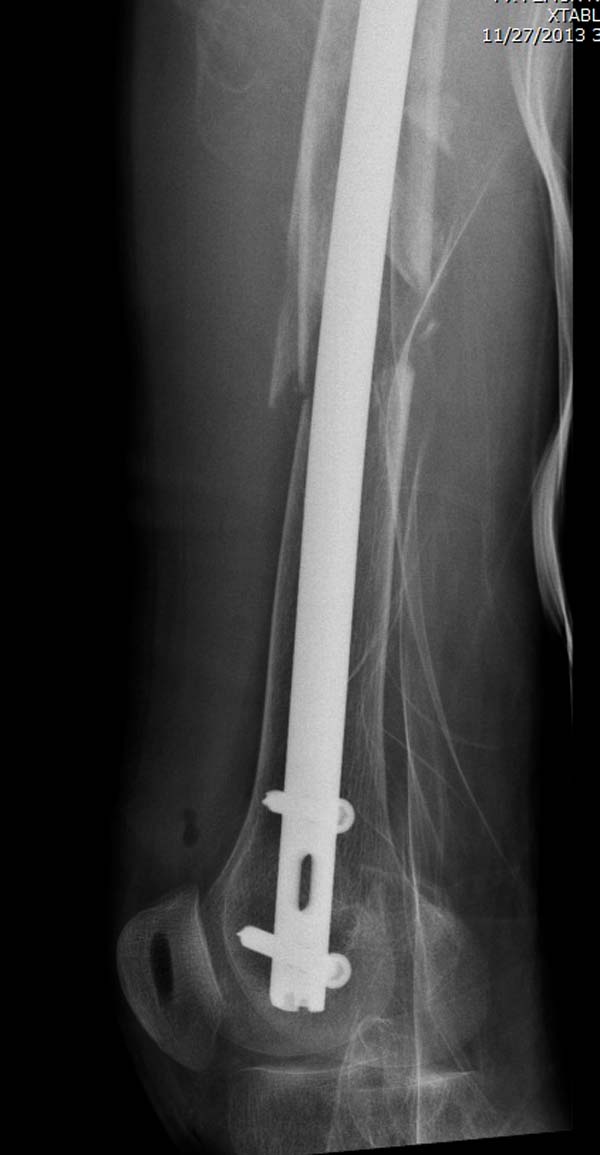

остаться до конца лечения, начал изучать язык... Для облегчения

транспортировки на второй день после поступления правая сторона была

фиксирована ретроградным гвоздем.

Гвоздь из ретроградного гвоздя DePuy в 15 мм получился немного тоньше,

чем у Российских коллег.

Операция не обошлась без казуса, при подготовке гвоздя произошла ошибка

в расчете. Пришлось коррегигировать по ходу операции, где длинный

дистальный отдел гвоздя срезали во время операции.

А так вроде первый американский опыт прошел удачно. У больного низкий

гемоглобин, который подправили во время операции переливанием крови.

надеюсь, контрагированные мышцы сохранит длину конечности. Контрольный

снимок показал устойчивую фиксацию.